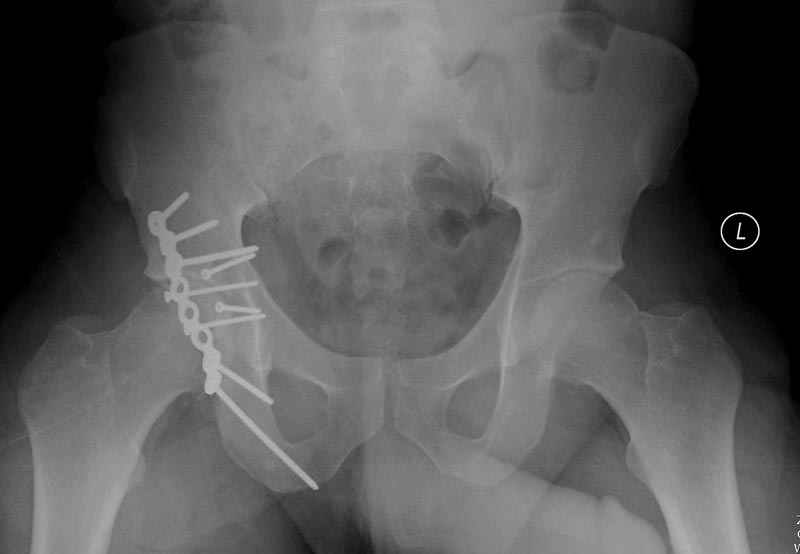

11:50 больной в послеоперационной, рентгенограмма N7, компьютерная томограмма в тот же день N8-10